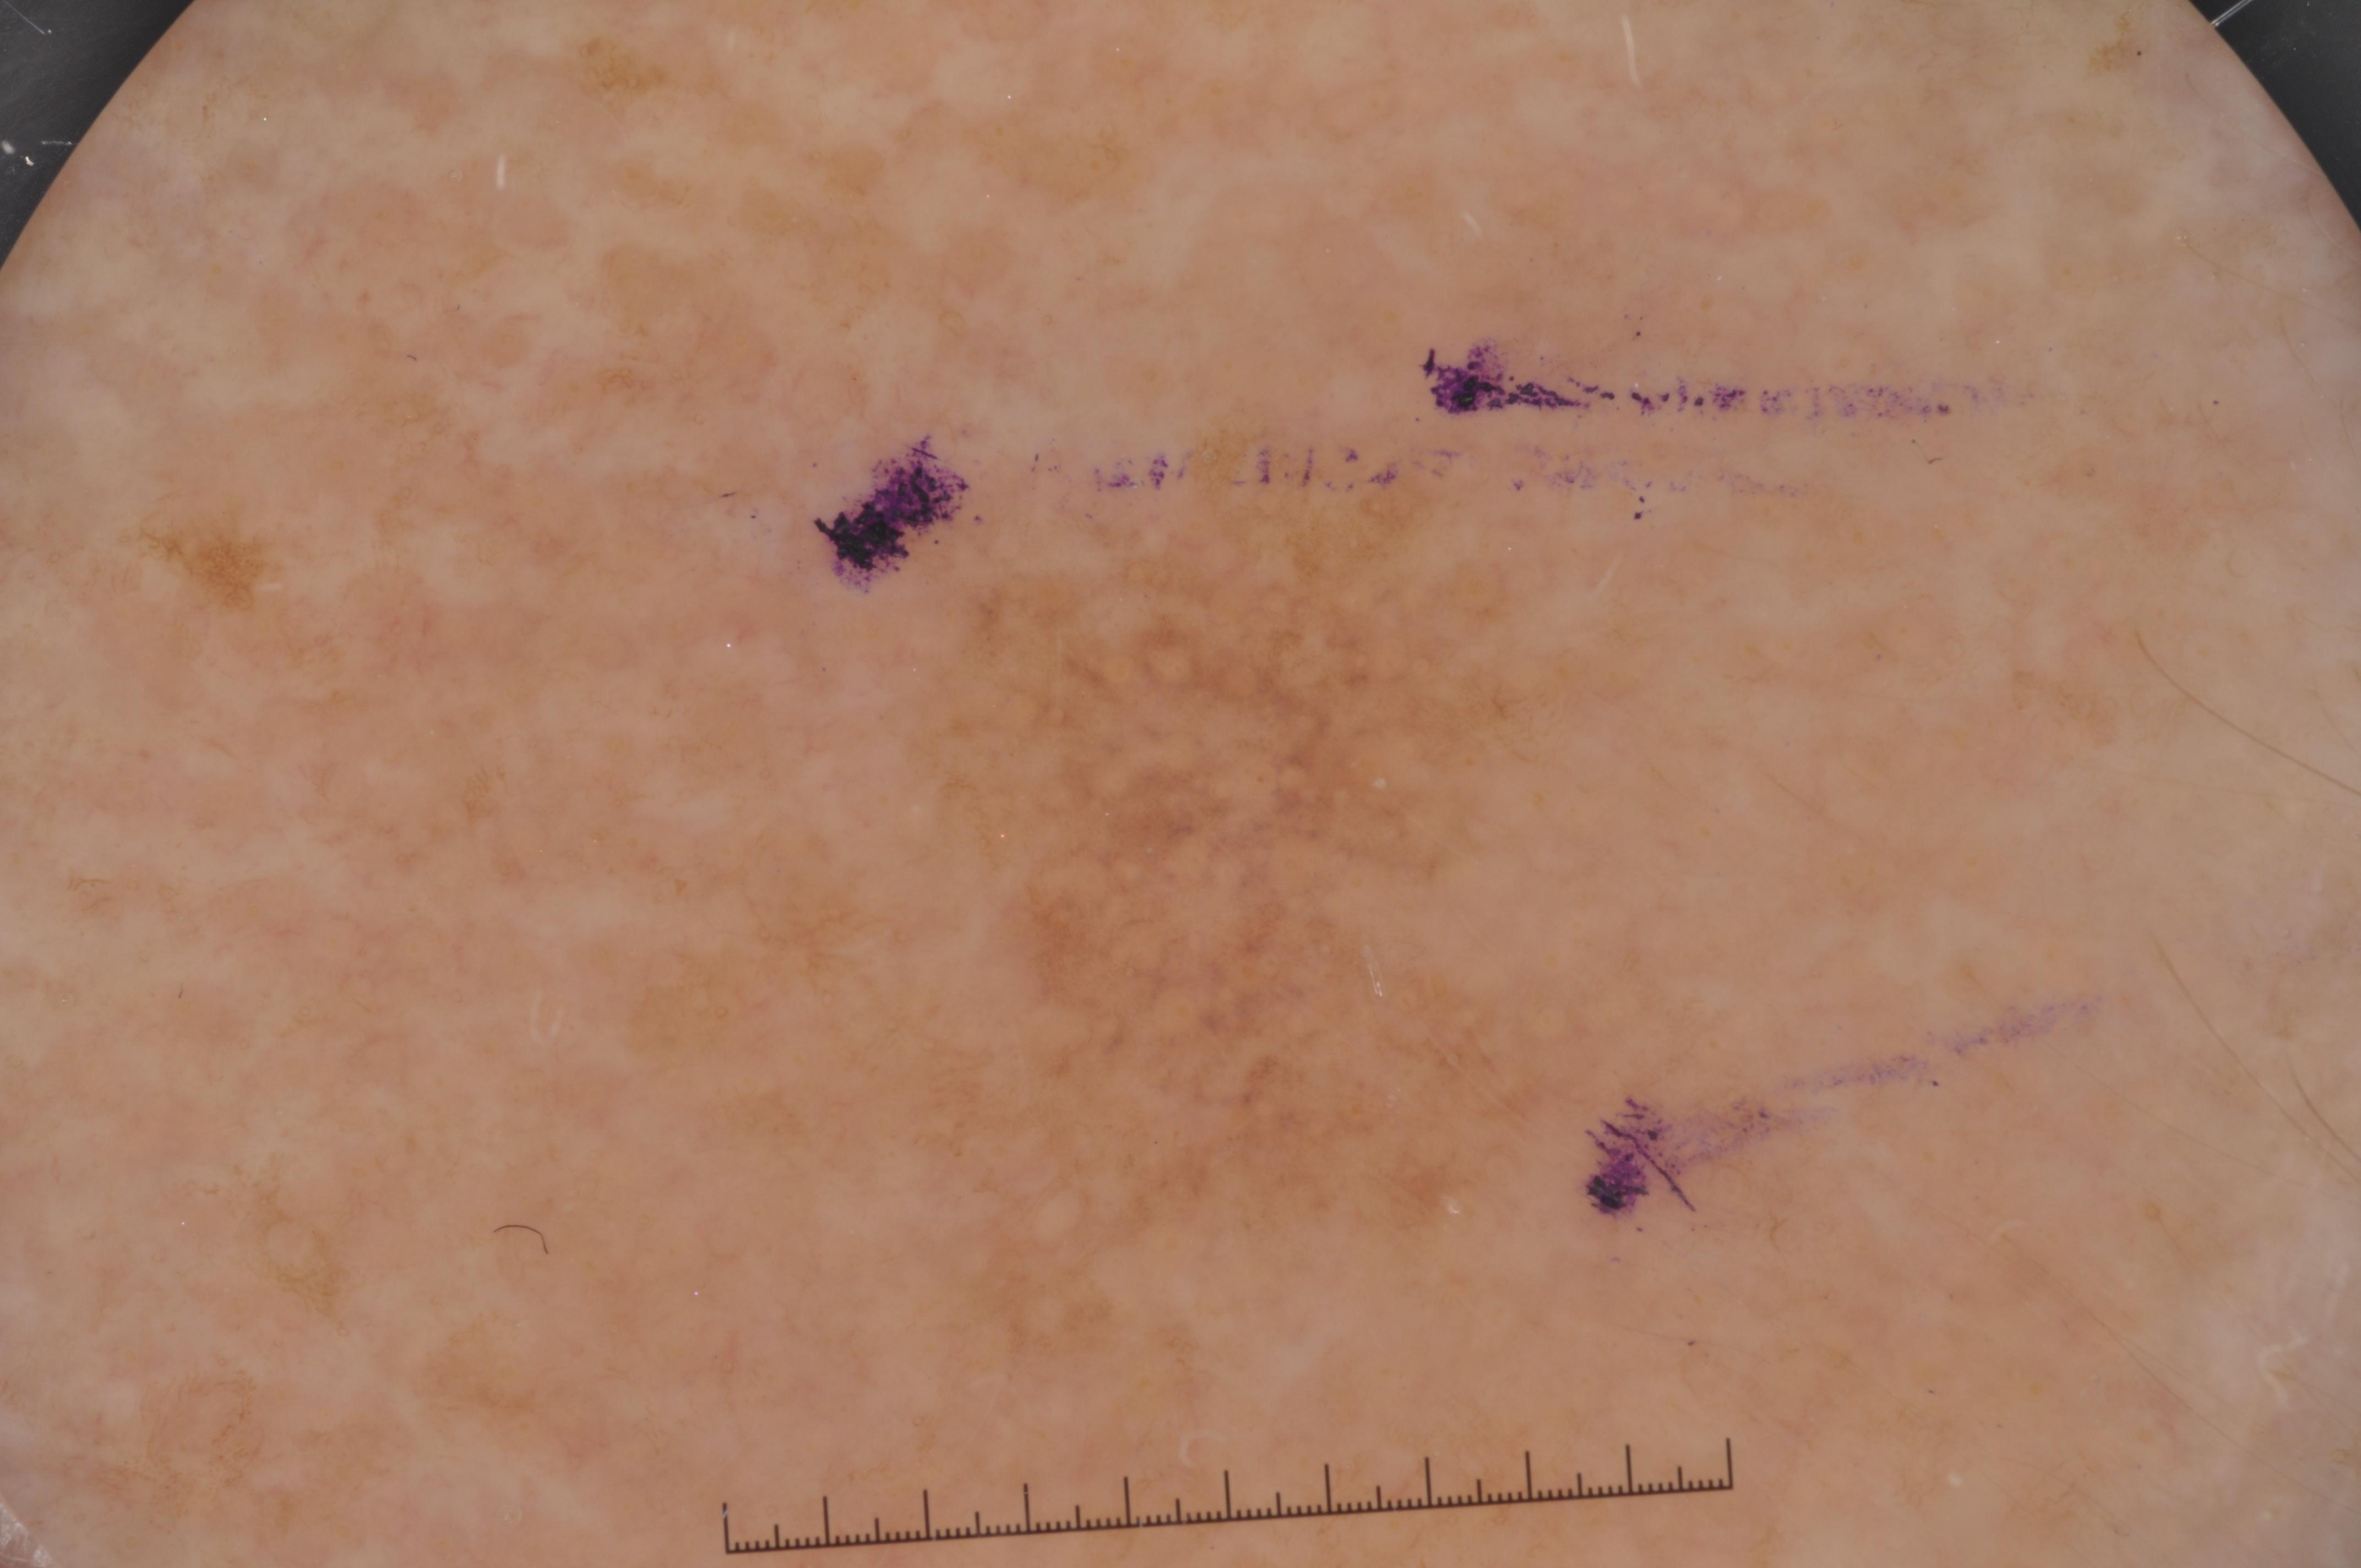

ISIC-DICM-17K (ISIC Dermoscopic Images and Clinical Metadata 17K) is a curated and balanced dataset derived from the International Skin Imaging Collaboration (ISIC) Archive Gallery. It comprises 17,060 dermoscopic images and clinical metadata (8,530 melanoma and 8,530 non-melanoma classes).

For more details, please follow the project’s GitHub repository: https://github.com/mmu-dermatology-research/isic-dicm-17k

This dataset was used in this study and benchmark to explore the effectiveness of multimodal learning for skin lesion classification:

S. Ahammed, X. Cui, W. Lu and M. H. Yap, "Skin Lesion Classification using Dermoscopic Images and Clinical Metadata: Insights from Multimodal Models," 2025 IEEE/CVF Conference on Computer Vision and Pattern Recognition Workshops (CVPRW), Nashville, TN, USA, 2025, pp. 222-230, DOI: 10.1109/CVPRW67362.2025.00027